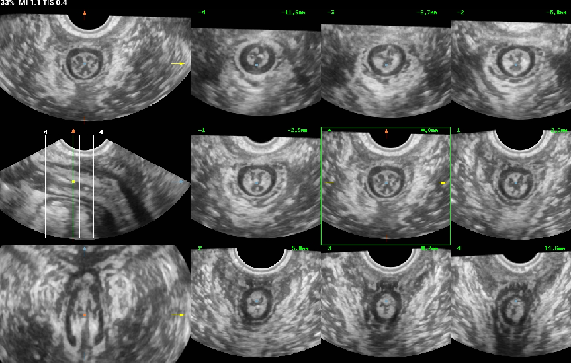

盆底超聲是利用超聲探頭經(jīng)會(huì)陰、陰道或直腸檢查,觀察在靜息、縮肛及Valsalva三種狀態(tài)下的盆腔臟器位置變化,結(jié)合多種成像方法(二維超聲、三維/四維容積超聲、斷層超聲成像)評(píng)估盆腔臟器脫垂程度、肛提肌裂孔大小及肛提肌、肛門內(nèi)外括約肌的完整性,同時(shí)能評(píng)估尿道、陰道及肛門周圍病變,也能用于盆底修復(fù)術(shù)前、術(shù)后及盆底康復(fù)療效的評(píng)估。具有無(wú)輻射、無(wú)創(chuàng)傷、可重復(fù)性好、實(shí)時(shí)動(dòng)態(tài)、價(jià)格低廉等優(yōu)勢(shì),有利于疾病的早期發(fā)現(xiàn)、早期診斷,在臨床癥狀出現(xiàn)前或癥狀較輕時(shí)通過(guò)物理治療來(lái)恢復(fù)盆底支持結(jié)構(gòu)功能,避免或者延緩手術(shù),提高患者生活質(zhì)量。